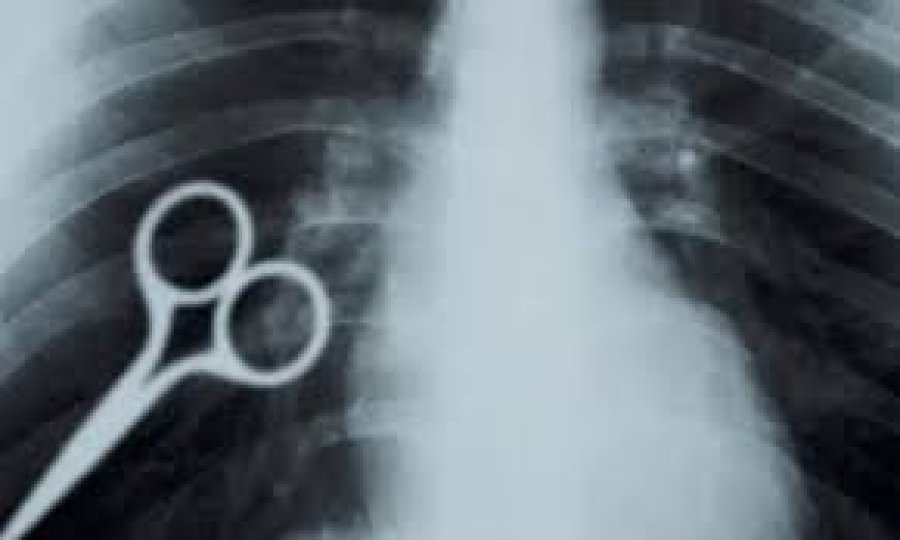

En la celda tragó una tijera

Quien cumple una condena desde 2019, tragó una tijera y lograron extraerla.

En la provincia de San Juan, un detenido que cumple condena desde 2019, se tragó una tijera y los médicos lograron extraerla, sin que el sujeto sufriera un inconveniente de temer, en cuanto a su salud.

Según se supo, no fue la primera vez que llevó a cabo un hecho similar, habida cuanta que se registra algo parecido en 2021.

Se trata de Axel Hernán Rojas, quien dijo que había concretado lo antes descripto, como un acto de protesta ante las condiciones carcelarias, que transita junto a otros presos.